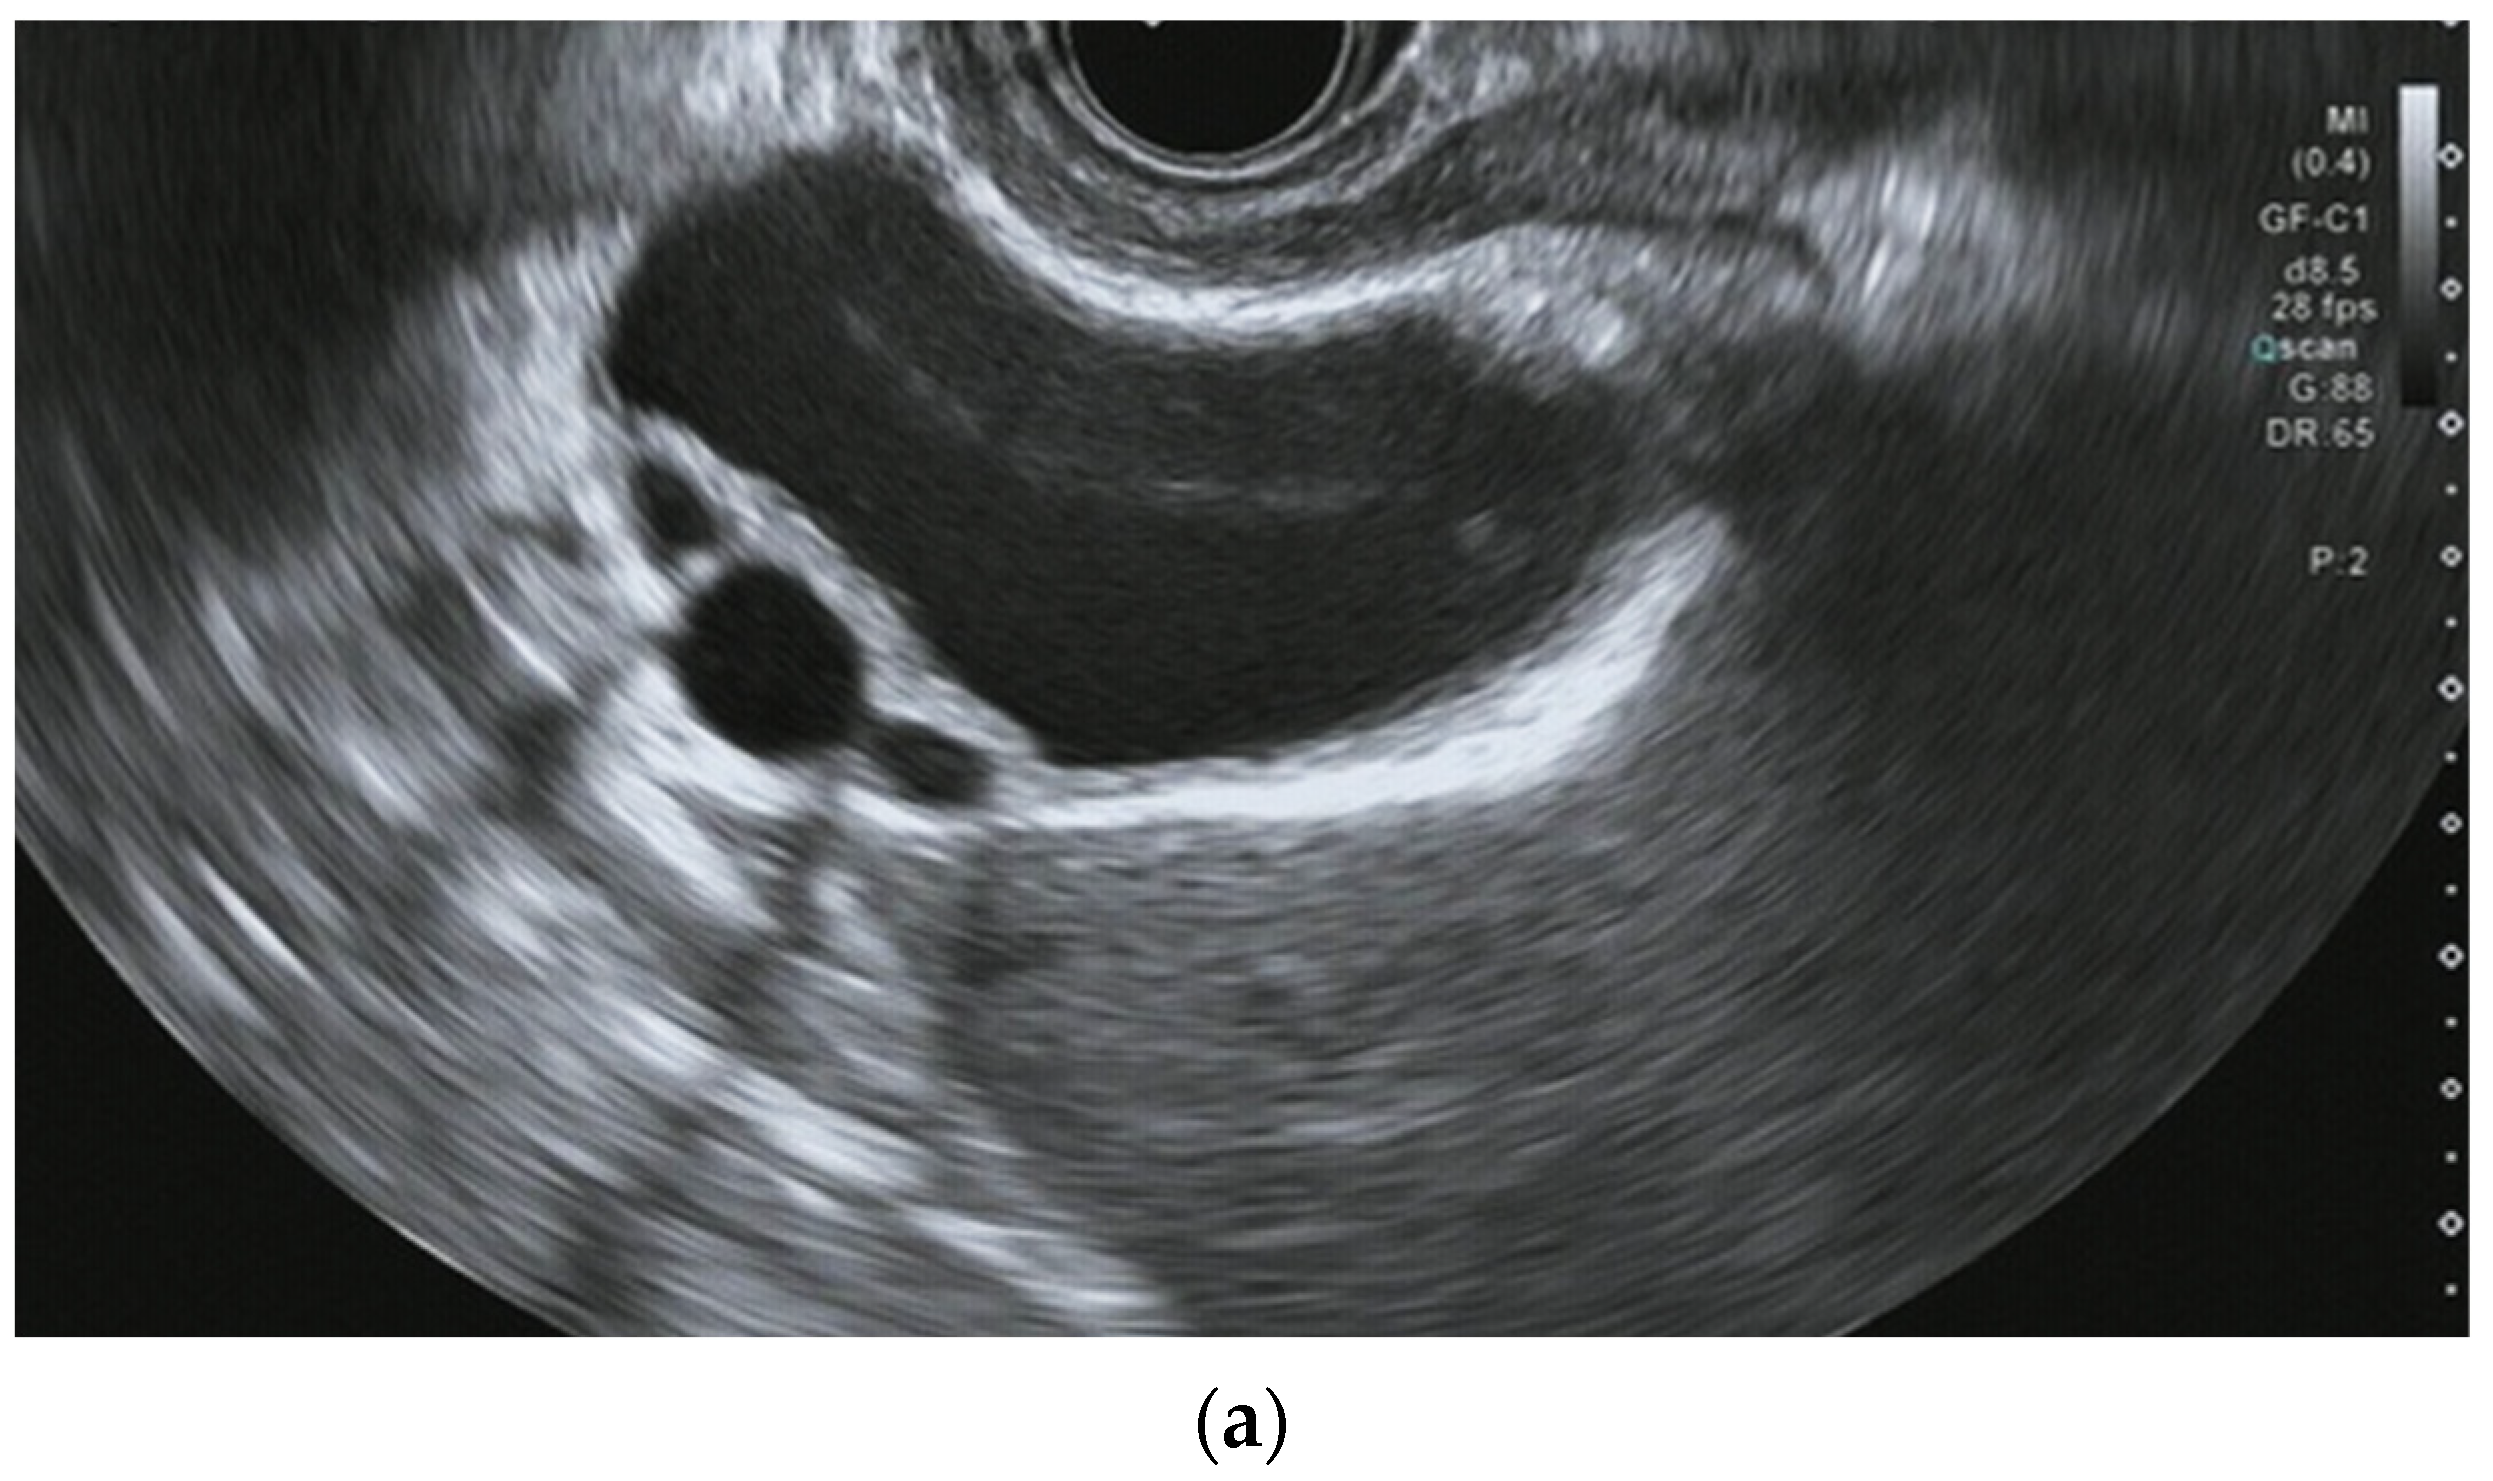

Characteristic EUS findings of ADM include comet-tail artifacts within the thickened wall and cystic anechoic spots, which are crucial for diagnosis [48] [Figure 5]. EUS can depict these findings in detail, whereas gallbladder carcinoma usually does not have such echoic findings. Findings suggestive of malignancy include wall thickening of 10 mm or more, heterogeneous internal echogenicity with regions of low echogenicity, and loss of layer structure [49] [Table 3].

Figure 5. Endoscopic ultrasound image of adenomyomatosis: (a) Thickened wall and cystic anechoic spots are visible. The cystic spots are showing Rokitansky-Aschoff sinuses.